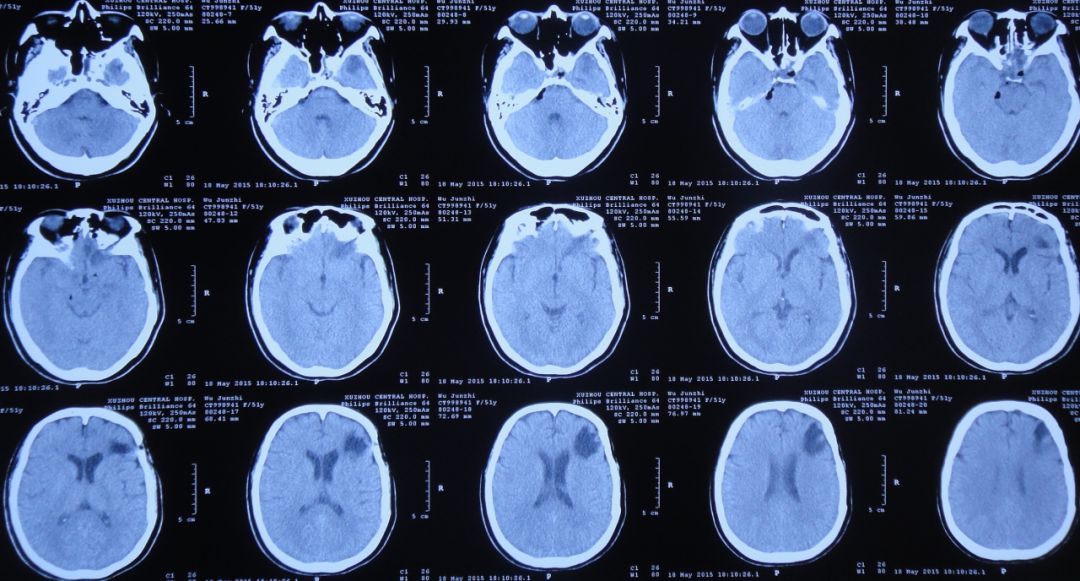

脑室引流术后第2天即2015年7月29日,患者神志恢复清楚,但仍有发热;复查头CT:脑室引流术后,脑室较前缩小(图12)。2天前腰穿留取的脑脊液细菌培养结果为白色假丝酵母菌,对氟康唑敏感,给予抗炎、抗真菌治疗。

图12:2015年7月29日头CT:脑室引流术后,脑室较前缩小

脑室引流术后第5天即2015年8月1日,患者体温恢复至正常,复查头CT:脑室扩张程度较引流术后减小(图13)。

图13:2015年8月1日头CT:脑室引流术后,脑室轻度扩张

拔除头部侧脑室外引流管后第2天即2015年8月3日,患者仍有脑脊液鼻漏,再次出现发热、头痛症状;复查头CT:脑室较前扩张,室旁水肿明显,颅内积气(图14),医生给予甘露醇脱水治疗。

图14:2015年8月3日头CT:脑室较前扩张,室旁水肿明显,颅内积气

2015年8月6日,复查头CT:脑室显著扩张,室旁水肿明显,颅内积气(图15)。患者仍有脑脊液鼻漏,但当地医院不予脑脊液漏修补治疗。

图15:2015年8月6日头CT:脑室显著扩张,室旁水肿明显,颅内积气

入院后第1天即2015年8月8日,复查头CT头:脑脊液蝶窦瘘征象。脑室扩张,双侧额叶片状密度减低,左侧额叶软化灶形成;脑沟、裂变浅;鞍上池及右侧脑室前角积气(图17)。

图17:2015年8月8日头CT:脑室扩张,鞍上池及右脑室前角积气

在入院后第2天即2015年8月13日,患者接受了“开颅脑脊液漏修补、右侧侧脑室腹部外引流术”。术后复查头CT:术区未见出血,脑室引流管位置良好(图18)。

图18:2015年8月13日头CT:术区未见出血,脑室引流管位置良好

开颅术后第4天即2015年8月17日,患者神清,咽喉部稍发痒、疼痛;复查头CT:右侧脑室前角及额骨颅板下气体密度影明显吸收,脑室扩张程度有所缓解,双侧额叶见片状混杂密度影,左侧额叶内示软化灶形成(图20)。

图20:2015年8月17日头CT:右脑室前角及颅板下气体明显吸收,脑室扩张较前缩小

开颅术后第26天即2015年9月8日,患者神清,咽喉部仍有异物感;复查头CT:脑室大小正常,鞍上池及鞍区积气(图21)。考虑患者仍存在脑脊液鼻漏,继续给予预防感染治疗。

图21:2015年9月8日头CT:鞍上池及鞍区积气

开颅术后第39天即2015年9月21日,患者神清,咽喉部仍有异物感;复查头CT:鞍上池、双侧侧脑室前角及鞍区积气(图22)。

图22:2015年9月21日头CT:鞍上池、双侧侧脑室前角及鞍区积气